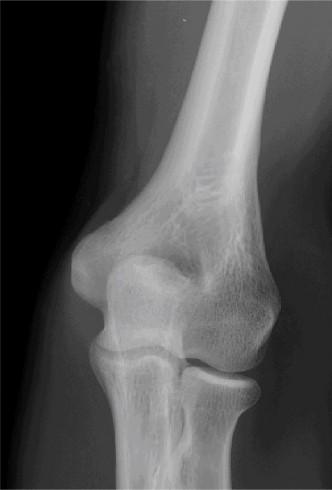

Anteroposterior (AP) and lateral radiographs of the right elbow were obtained.

Initial AP and Lateral Radiographs:

These views clearly demonstrated a posterior dislocation of the ulnohumeral joint. The olecranon was positioned posterior to the distal humerus. Crucially, the radiographs revealed associated fractures.

- There was a comminuted fracture of the radial head (Mason Type III).

- A significant coronoid process fracture was identified, involving approximately 50% of the coronoid height, consistent with a Regan-Morrey Type II fracture.

- Evidence of avulsion fractures from the medial epicondyle (consistent with MCL injury) and lateral epicondyle (consistent with LCL complex injury) were also noted, indicating extensive soft tissue disruption.

(Representative initial lateral radiograph demonstrating posterior elbow dislocation with associated coronoid and radial head fractures.)

Given these findings, a diagnosis of a terrible triad injury of the elbow was made.

Clinical & Radiographic Imaging